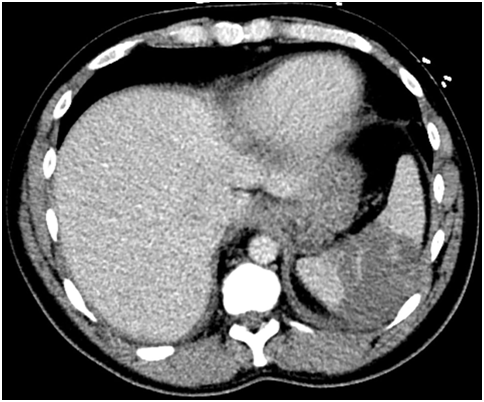

A 31-year-old Caucasian man presented to the hospital with 4day-history of left upper quadrant abdominal pain and left sided pleurisy. He had recently failed therapy for chronic HCV mono-infection, genotype 1a, with fibrosis score of F0. He admits to using intravenous recreational drugs. Vital signs were normal except for heart rate of 130/min. The abdomen was tender in the left upper abdominal quadrant with no of peritoneal irritation. Initial blood investigations revealed leukocytosis of 21.3x103/µl with normal renal function and liver enzymes. Computed tomography of the abdomen with IV contrast showed a large splenic infarct (Figure 1). He had no recent abdominal trauma or abdominal surgery. Streptococcus constellatus was cultivated from two sets of blood cultures on day three. Comprehensive workup excluded mononucleosis, pancreatic disorders, HIV, autoimmune/collagen vascular disease, sickle hemoglobinopathies, malignant hematologic disorders (normal peripheral blood smear, SPEP and flow cytometry), hepercoagulable state (normal protein C or protein S; normal lupus anticoagulant, factor V, prothrombin). Patient had no signs of ARDS, sepsis, septic shock or toxic shock syndrome. Patient no recent cardiac catheterization (angiographic embolization), sclerotherapy of esophageal varices, abdominal surgery (pancreatectomy, or liver transplant), vasopressin infusion, or embolization for splenic hemorrhage. Echocardiogram showed the presence of 2.5x1.5cm2 vegetation of the aortic valve with perforation, severe regurgitation and aortic root abscess (Figure 2). Magnetic resonance imaging (MRI) of the brain showed numerous brain abscesses, without mass effect or midline shift. This case was complex and Duke’s criteria were used to make the diagnosis of IE. The patient received aortic valve replacement and his post-operative course was uneventful. Administration of ertapenem was continued for 8 weeks. The patient had full neurological recovery and repeat MRI of the brain showed complete resolution of the abscesses. Follow-up echocardiogram showed no thrombosis or vegetation of the bioprosthetic valve.

Figure 1A) Computed tomography of the abdomen.

Figure 1B